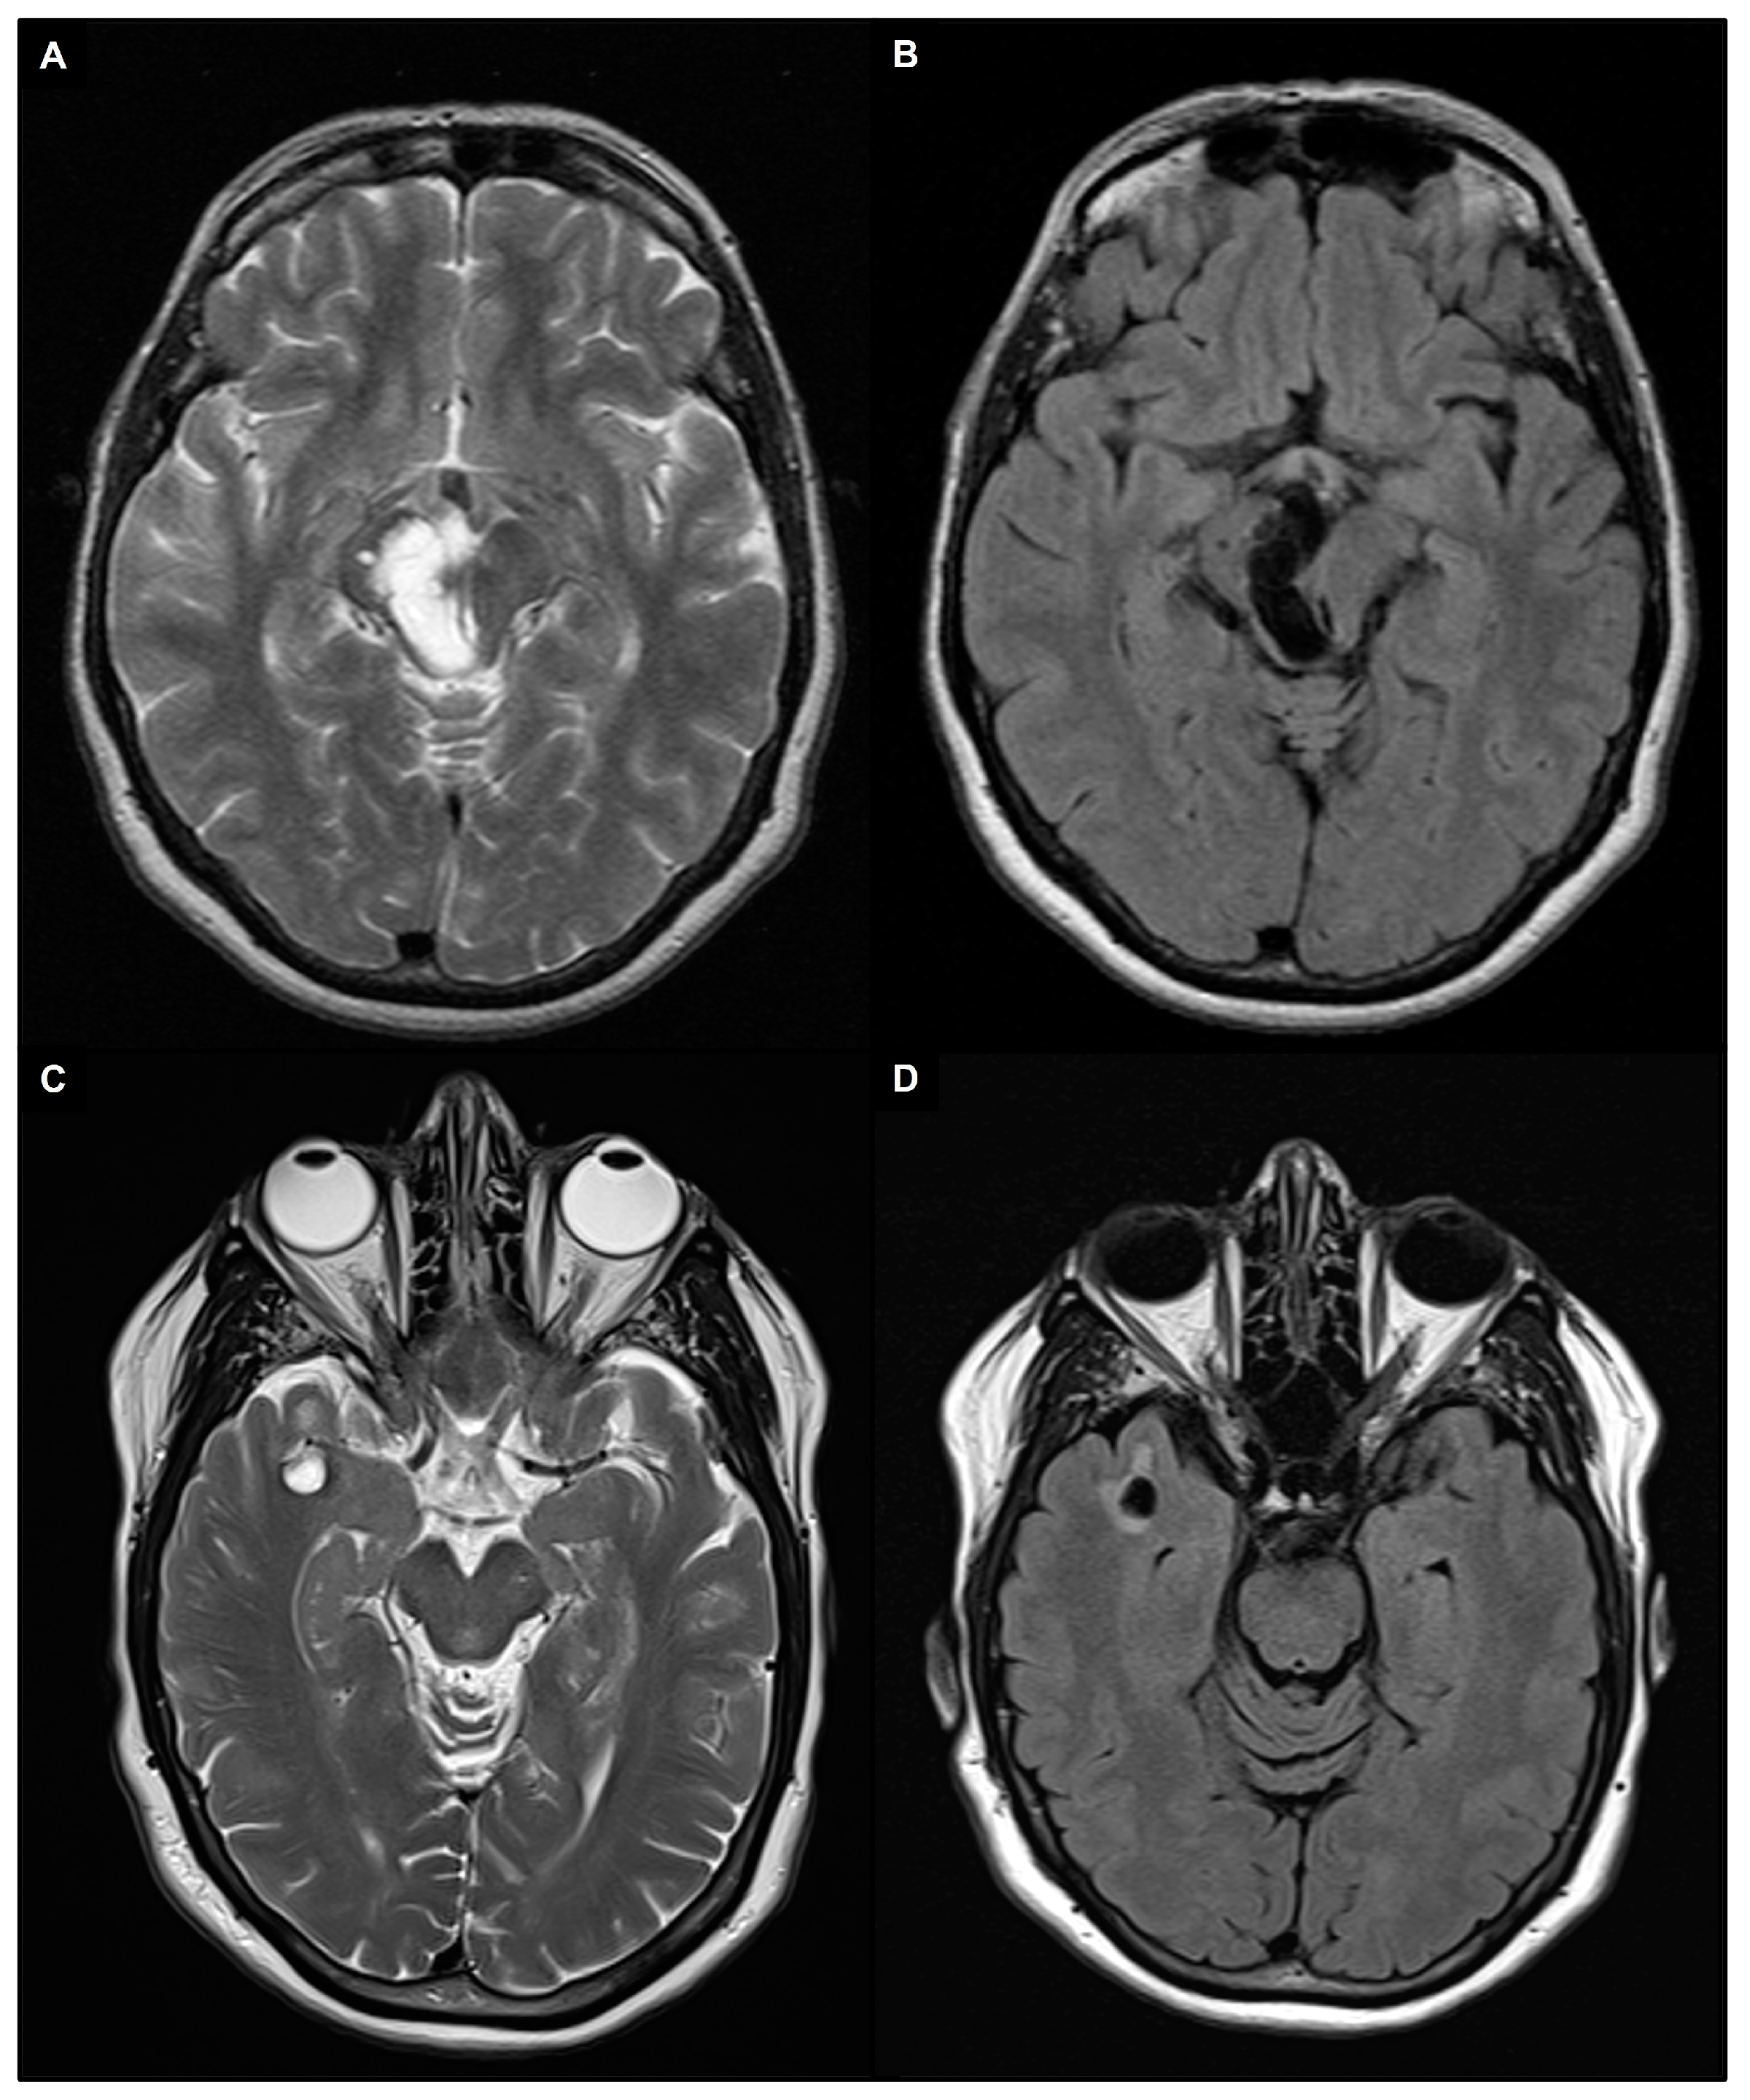

- Wardlaw, J.M.; Smith, E.E.; Biessels, G.J.; Cordonnier, C.; Fazekas, F.; Frayne, R.; Lindley, R.I.; O’Brien, J.T.; Barkhof, F.; Benavente, O.R.; et al. Neuroimaging Standards for Research into Small Vessel Disease and Its Contribution to Ageing and Neurodegeneration. Lancet Neurol. 2013, 12, 822–838. [Google Scholar] [CrossRef]

- Kwee, R.M.; Kwee, T.C. Virchow-Robin Spaces at MR Imaging. Radiogr. Rev. Publ. Radiol. Soc. N. Am. Inc. 2007, 27, 1071–1086. [Google Scholar] [CrossRef]

- Rudie, J.D.; Rauschecker, A.M.; Nabavizadeh, S.A.; Mohan, S. Neuroimaging of Dilated Perivascular Spaces: From Benign and Pathologic Causes to Mimics. J. Neuroimaging Off. J. Am. Soc. Neuroimaging 2018, 28, 139–149. [Google Scholar] [CrossRef] [PubMed]

- Kwee, R.M.; Kwee, T.C. Tumefactive Virchow-Robin Spaces. Eur. J. Radiol. 2019, 111, 21–33. [Google Scholar] [CrossRef] [PubMed]